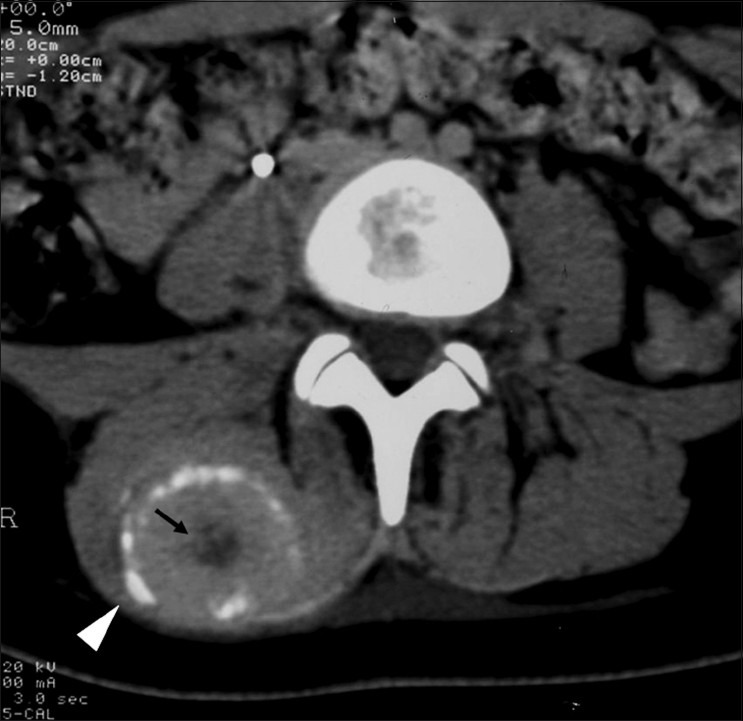

CT may be useful in the visualization of a lesion. Figure 3 demonstrates a lesion posterior to the right acetabulum. It demonstrates a partially corticated periphery and partial cleft separating the lesion from the acetabulum. Figure 4 is an interesting example of an MO lesion in the paraspinal musculature, with ossified periphery and lucent center.

Radiographically, findings may appear as early as 3 to 4 weeks post-injury. Initially, there may be a hazy increase in density in the soft tissues. With time, the bone formation will be noted at the periphery of the lesion, forming a shell. Progressive ossification of the lesion may follow, characteristically with a denser periphery and a relatively lucent central region. The lesion is usually mature at 2-6 months. Typically, a radiolucent cleft is seen separating the lesion from the underlying bone. After reaching maturity, the lesion usually will regress in size. This appearance is a key to differentiating myositis ossificans from parosteal osteosarcoma, which is the main differential diagnosis. These soft tissue sarcomas tend to have greater density at the center of the lesion and a less dense periphery. Lesion biopsy is not a reliable differentiator between sarcoma and MO, as histologically the two may be very similar, and, thus, an MO lesion should not be biopsied.